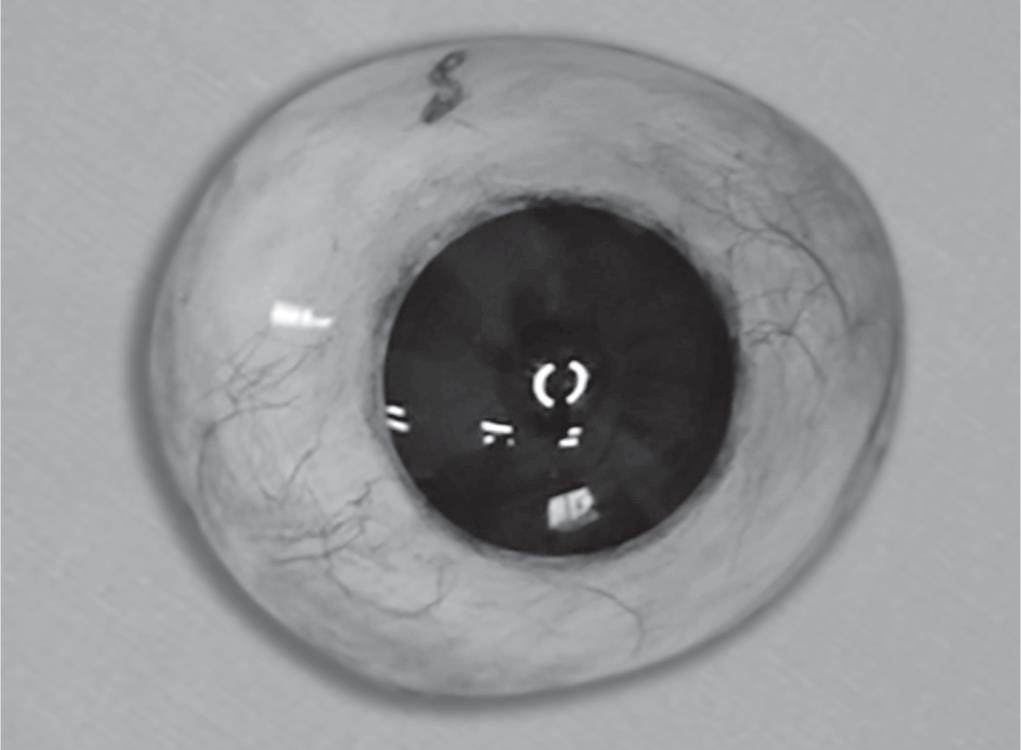

Finishing and Polishing

Finishing and polishing was done using finishing burs, pumice and buff to get a natural glossy appearance of the artificial eye (Fig. 15).

Fig. 15: Ocular prosthesis after finishing and polishing